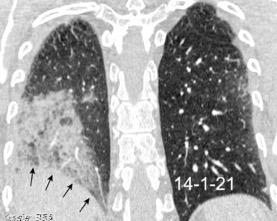

< Volumen pulmonar

Síndrome antisintetasa

(Miositis anti Jo-1).

Artralgias migratorias, Miositis, “Manos de mecánico”, Raynaud y Enfermedad

intersticial pulmonar (>70%).

Waseda Y et al.. Eur J Radiol. 2016